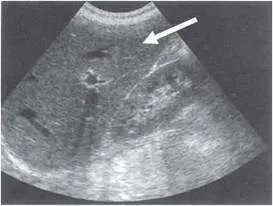

下圖右肋間足側掃描超音波檢查圖像中,箭頭所指為:

圖片為扇形(sector)探頭掃描所呈現的右肋間足側切面。影像中可見:

- 主要結構:影像近場(上方)佔據大部分視野的是一個質地均勻、中等回聲強度的大型實質器官,其內可見多條細線狀高回聲結構(對應門靜脈及其分支的血管壁),此為肝臟(liver)的典型超音波表現。

- 白色箭頭所指:箭頭指向影像左上角,即肝臟的上緣/膈面區域,為肝臟實質(hepatic parenchyma)。

- 回聲特徵:正常肝臟呈現中等、均勻的細點狀回聲(medium-level homogeneous echogenicity),略高於腎臟皮質回聲,可作為相互比較的參考。

- 解剖意義:右肋間掃描時,探頭置於右側肋間隙,可避免肋骨聲影干擾,完整呈現肝臟右葉。深部可見膈肌(diaphragm)形成的高回聲弧線。

此影像中不符合腎臟(腎臟呈豆形、有高回聲腎竇)、胰臟(位於腹部深部、胃後方,右肋間不易見到)、膽囊(呈橢圓形無回聲囊腔)的外觀。